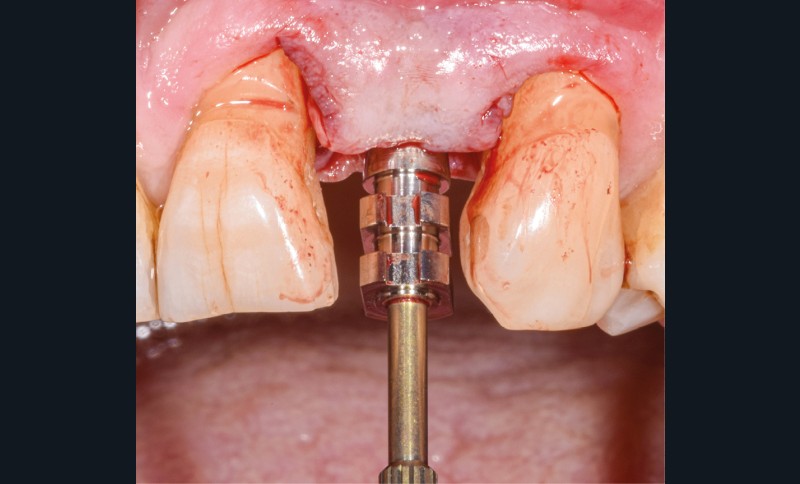

Un patient de 62 ans se présente en consultation afin de réaliser les coiffes prothétiques des dents 12 et 22. La 12 présente une restauration par prothèse transitoire non adaptée. Un implant au niveau de la 22 a été posé par un autre praticien selon une technique chirurgicale en deux temps. Le praticien a adressé le patient pour la réalisation prothétique. L’option de bridge collé cantilever mono ailette n’avait pas été retenue ou proposée selon une technique chirurgicale en deux temps. Le patient souhaite rétablir l’esthétique et la fonction de ces deux dents uniquement.

La proposition thérapeutique retenue par le patient est donc une réhabilitation par couronne céramique sur 12 (dento-portée) et 22 (implanto-portée). Ce choix thérapeutique impose de concevoir des dents qui s’intègrent au mieux dans l’harmonie du sourire, tout en étant conscient des limites d’un tel traitement.